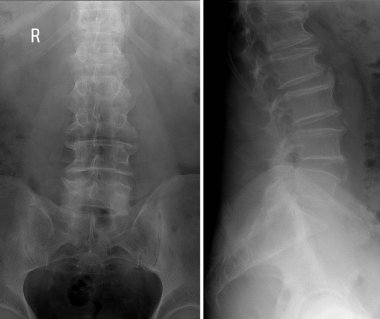

Sırt ve kereste omurgasının röntgen ışınları spondilotik değişimleri, sırt ve kereste dikenlerinin düzleştirilmesini, omurgalar arası disk alanlarının bozulmamış olduğunu, sırt ve kereste dikenlerinin Spondylosis 'inin bozulmamış olduğunu gösterir.